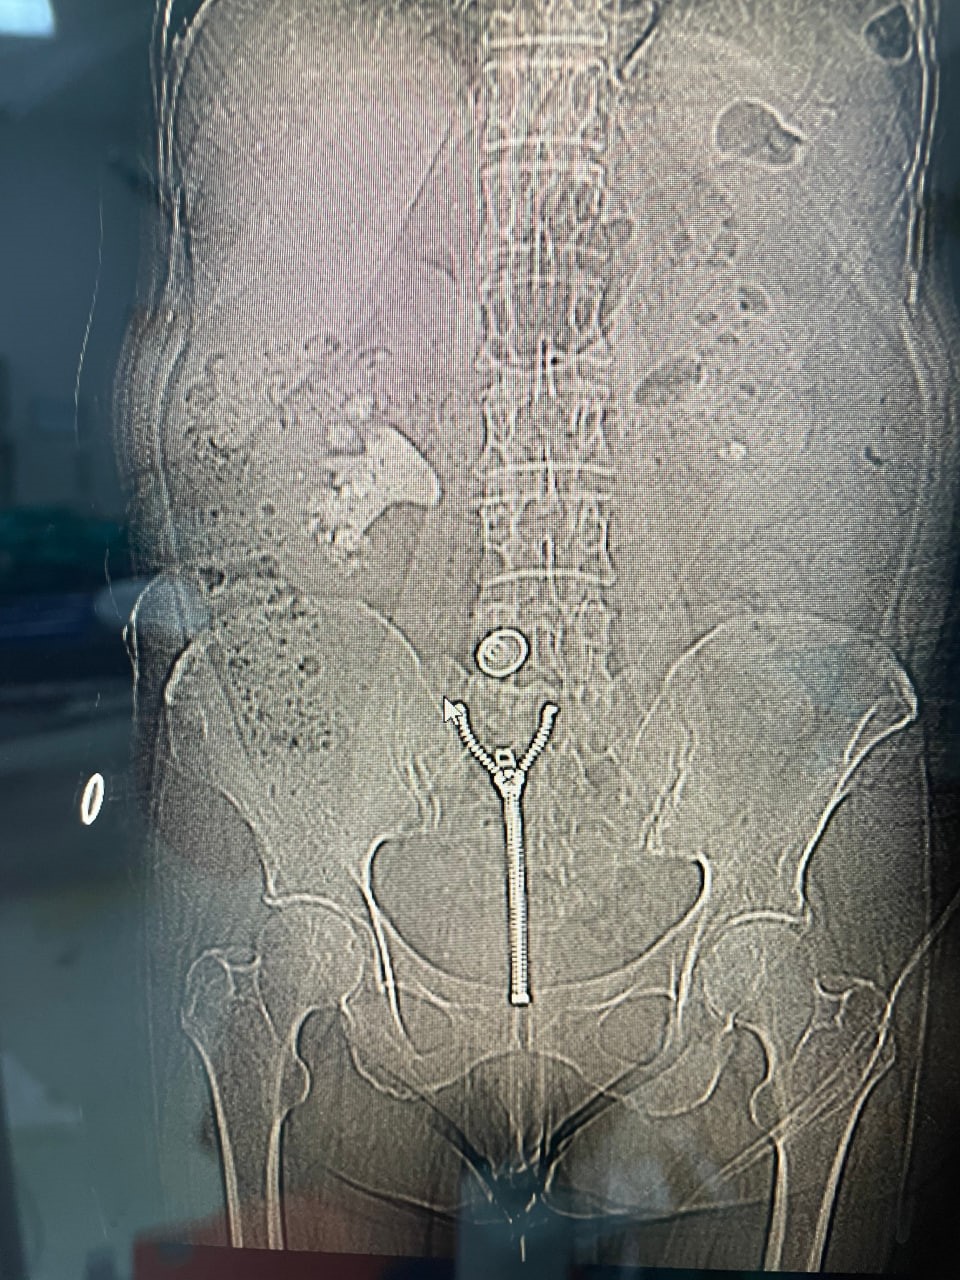

Operasyonu gerçekleştiren Üroloji Kliniği Uzmanı Dr. Mehmet Levent Akbulut, taşın büyüklüğüne dikkat çekerek, "Hastamızın böbreğinde yaklaşık 8 santimetre çapında büyük bir taş vardı. Tıpta bu tabloya ‘staghorn’, yani geyik boynuzu taşı diyoruz. Eğer bu taş alınmasaydı, böbrek fonksiyonunu tamamen kaybedebilirdi. Biz de perkütan nefrolitotomi adını verdiğimiz kapalı yöntemi tercih ettik. Tomografi yardımıyla planlama yaparak, böbreğe küçük bir delikten girip taşı parçalara ayırarak tamamen temizledik. Ameliyat sonrası hastamızın böbreği taşsız hale getirildi" dedi. Dr. Akbulut, söz konusu yöntemin açık ameliyata göre çok daha hızlı iyileşme süreci sağladığını ve bu tür kompleks operasyonların Malatya’da başarıyla gerçekleştirilebildiğini belirtti.

"Yarım su bardağı kadar taş çıktı"

Başarılı operasyon sonrası kısa sürede sağlığına kavuşan Ülkü Sabaner, "Bir akşam şiddetli sancıyla acile başvurdum. Yapılan kontrollerde büyük bir taşım olduğu ortaya çıktı. Doktorlarım kapalı yöntemle ameliyat edilebileceğini söylediler. Pazartesi günü ameliyat oldum, üç gün sonra taburcu oldum. Çıkan taş neredeyse yarım su bardağı kadardı. Açık ameliyata göre çok daha kolay bir süreçti. Bir hafta içinde normal hayatıma geri döndüm. Başta doktorum olmak üzere tüm sağlık çalışanlarına teşekkür ediyorum." ifadelerini kullandı